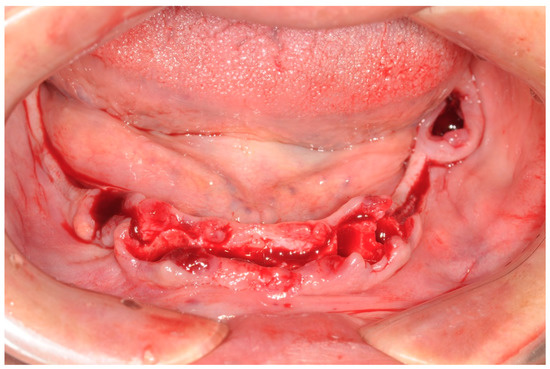

All patients received implants with a grit-blasted and acid-etched surface (Ossean®; Intra-Lock International®, Inc., Boca Raton, FL, USA) that were placed using a sterile surgical technique, as recommended by the manufacturer. Maximum care was taken to place the implants, regardless of whether they were inserted in an edentulous ridge or an extraction site, with a minimum insertion torque of 35 Ncm and not exceeding 50 Ncm (Figure 3).

The peri-implant bone defects in the extraction sockets were grafted with a cortico-cancellous porcine bone (GTO, Tecnoss-Dental, Giaveno, Italy). Flat abutments (FlatOne®; Intra-Lock International®, Inc., Boca Raton, FL, USA) were then connected to the implants, and the flap was sutured (Figure 4).

Figure 3. Implants were inserted, and flat abutment connected.

Figure 4. Flat abutment connection.